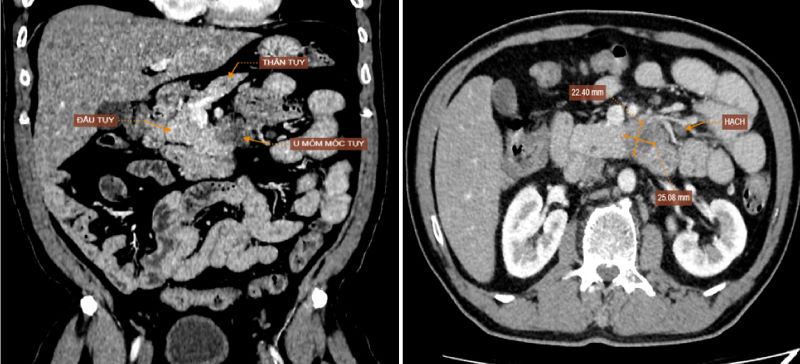

Kết quả nội soi không ghi nhận bất thường, tuy nhiên hình ảnh CT cho thấy khối u vùng mỏm móc đầu tụy có dấu hiệu xâm lấn động mạch mạc treo tràng trên và tá tràng. Đồng thời phát hiện thêm tổn thương đa ổ ở gan, hạch ổ bụng và nốt đặc ở thùy dưới phổi phải – nghi ngờ di căn xa. Kết quả sinh thiết sau đó xác nhận bệnh nhân mắc ung thư biểu mô tuyến tụy giai đoạn T4N2M1 (giai đoạn cuối). Bệnh nhân được chuyển sang cơ sở chuyên khoa ung bướu để tiếp tục điều trị.

Hình ảnh chụp cắt lớp vi tính ổ bụng phát hiện khối u vùng mỏm móc đầu tụy.